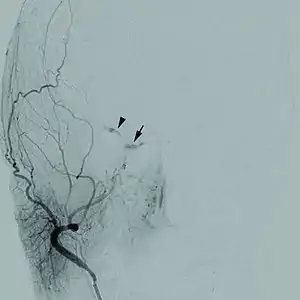

| Cerebrovascular disease | |

|---|---|

![]() | |

| Cerebral angiogram of a carotid-cavernous fistula | |